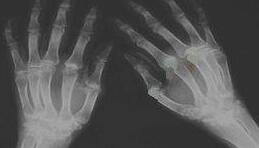

手指关节开始出现红肿僵硬的现象,早上起来时偶尔还会伴有将近一个小时晨僵的现象,在医院进行了检查,被确诊为类风湿性关节炎。...[详细]

吴女士20+年前出现双手、双足、双小腿疼痛不适,曾在当地医院就诊,口服药物控制病情,效果不佳,现右踝关节疼痛不适,双手指间关节疼痛不适,双上肢、双下肢疼痛不适,逐在老公陪同下来院就诊。 (图:王怀...[详细]